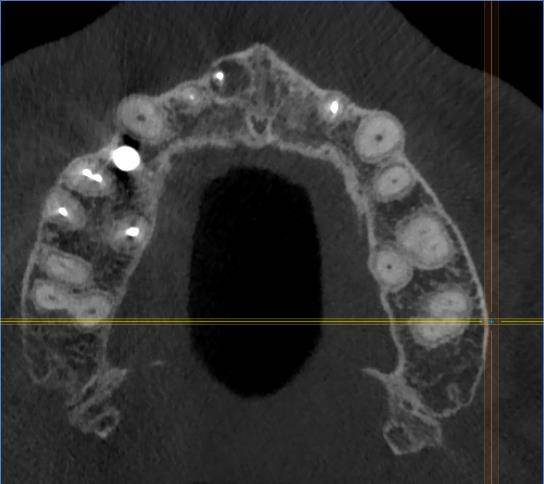

Есть зуб 11 (с СВШ) с восспалением около корня. До брекетов тоже было.

Перед протезированием предлагают перелечить каналы через корень с извлечением СВШ и последующим восстановлением (не понятно правда с СВШ или уже без него. Без СВШ зуб прям под корень может обломаться) под коронку.

До этого предлагали резекцию. Как в итоге лучше, через корень или резекцию?11-2.jpg.ba542aa82cfd6ddaad3fb9e234b99d99.jpg11.jpg.a34f40916e8e638d622001c50fff6e3a.jpg11-3.jpg.7a281f5893f8e6440937071fda10d523.jpg11-4.jpg.6a62c56e00cfdfa00cf35b7e276fd908.jpg